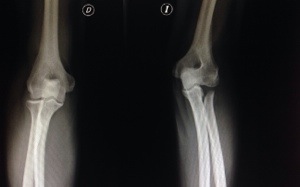

Vean seguidamente el ejemplo de un paciente que presentaba una lesión de Essex-Lopresti con conminución de la cabeza de radio, al que le fue practicada de urgencias una resección de la cabeza de radio. A los 2 meses presenta un acortamiento tal del radio que el paciente tenía una prono/supinación bloqueada a 0grados.